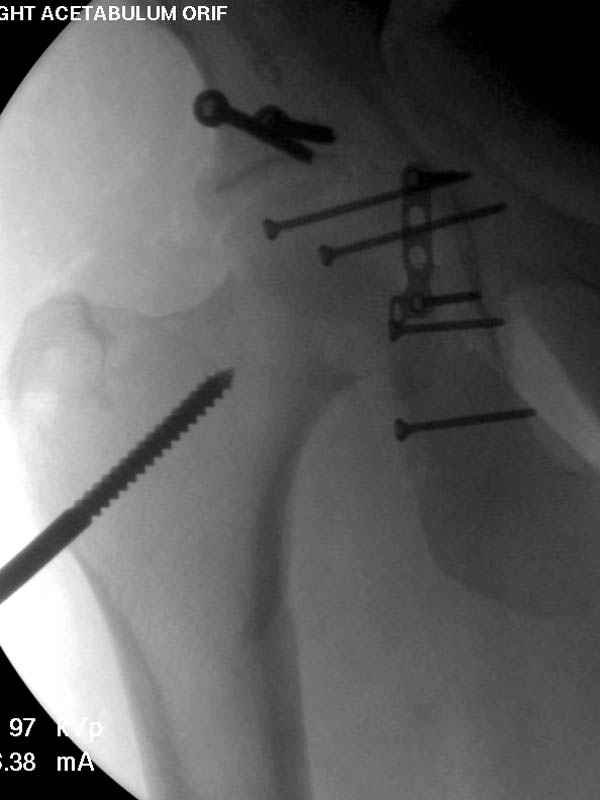

Имя     : 1 Proximal hum+acetabulum CRM.jpg

Url     : http://weborto.net:8080/pipermail/ortho/attachments/20071130/be03ce6b/attachment-0004.jpg